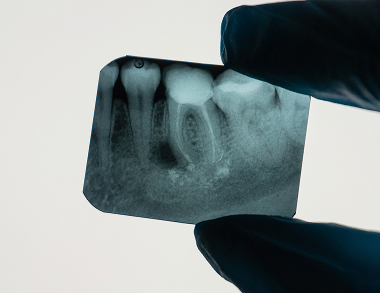

Dental X-rays are essential diagnostic images that use low levels of radiation to capture detailed pictures of your teeth, roots, and jawbone. They reveal hidden structures and problems not visible during a regular oral exam.

Common types include bitewing X-rays to check for cavities between teeth, periapical to view the entire tooth root, and panoramic images for a broad overview of the jaws, teeth, and joints.